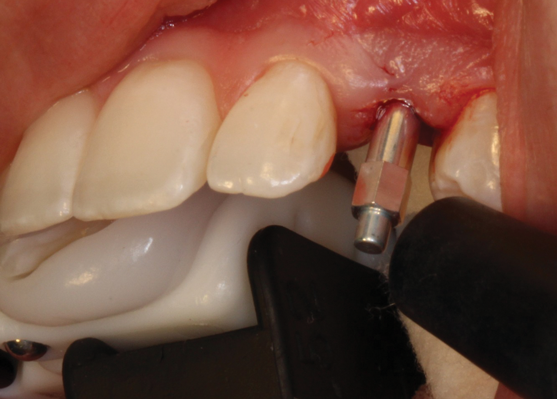

(38.) The opaqued titanium provisional abutment was gently tightened onto the implant.

Figure 38

(39.) The composite tooth shell was modified to fit around the abutment, positioned intraorally, and bonded to the abutment with flowable composite in the incisal half.

Figure 39